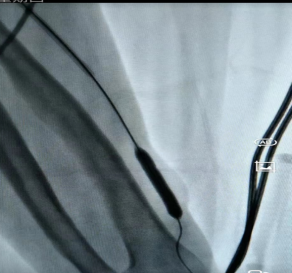

对于长期做透析的朋友来说,血管通路就是“生命线”,这条“路”一旦堵了(比如狭窄、长血栓),透析效果会变差,严重的还可能危及生命。以前遇到这种情况,不少人担心要“开大刀”,现在有了更简单的办法。 贵州航天医院肾脏风湿科开展了一项微创技术——血管通路介入治疗(用一根细针、一根微导管,顺着血管把堵塞的地方“疏通”开),不用大切口,也能解决内瘘狭窄、血栓、闭塞这些麻烦事。 这项技术是怎么做的? 医生在影像设备(彩超、DSA)的实时引导下,从皮肤上扎一个小针眼,把导管送到血管病变的位置,然后用球囊撑开狭窄的地方、或者溶掉血栓、必要时放个小支架,整个过程创伤小、恢复快、还能反复做。 主要能解决哪些问题? ※动静脉内瘘狭窄或闭塞:做球囊扩张术(PTA),是目前首选的办法。 ※内瘘里长了血栓同时伴有狭窄:溶栓+球囊扩张。 ※中心静脉(比如胸口附近的血管)狭窄或闭塞:球囊扩张或放支架。 ※需要放透析长期导管但位置不好放:精准置管。 哪些人适合做? 1.透析时血流量不够、静脉压力高、穿刺越来越困难。 2.彩超检查发现内瘘狭窄超过50%,或者内瘘发育不好、术后又窄了。 3.内瘘完全堵死,想尽量保住原来的血管。 4.手臂或脸肿了,可能是中心静脉堵了。 5.自身血管条件差,反复置管失败,或者身体受不了开刀手术。 6.目前脖子上或大腿上带着长期透析管,想拔掉管子改用自己的内瘘。 这项技术好在哪? ☑微创损伤小:就一个小针眼,几乎不留疤,局部麻醉就行,对身体影响小。 ☑看得清,打得准:彩超或DSA实时引导,医生能清楚看到血管,避开重要部位。 ☑恢复快:多数患者做完手术当天就能下床活动,内瘘很快就能再用上,不用等。 ☑省着用血管:球囊扩张可以反复做,尽量保住自己的血管。 ☑能重复治疗:以后万一再堵了,还可以再做介入,不用“一刀切”重新建一条通路。 ☑减少感染风险:成功救回内瘘后,很多患者可以拔掉临时或长期的透析导管,感染风险更低,也保护了中心静脉。 透析小常识: 1.透析就是帮助受损的肾脏“洗血”,清除体内多余水分和代谢废物,多数人每周做2-3次,每次约4小时。 2.内瘘是透析患者手臂上通过手术将动脉和静脉连接起来的一种血管通路,摸上去会有“嗡嗡”的震颤感,是透析治疗的关键通道,平时要护好内瘘——每天用手摸一摸震颤是否正常,别压着内瘘侧手臂睡觉,不提重物,不在这侧抽血或量血压。 3.饮食上注意少喝水(两次透析间体重增长不超过干体重的3%-5%),少吃盐和含磷高的食物(如坚果、动物内脏、可乐),适当吃鸡蛋、瘦肉、鱼肉等优质蛋白。 4.如果发现内瘘震颤变弱或消失、手臂肿胀、透析时血流量不足,立即告诉医生。 注:部分图片来源于网络,如有侵权,请联系删除。 贵州航天医院 肾脏风湿科专家简介 冯远军 肾脏风湿、肝胆外科党支部书记,肾脏风湿科主任,主任医师 临床擅长:对慢性肾脏病、急性肾损伤、急慢性肾小球肾炎、肾病综合症、风湿性疾病、间质性肾炎、肾小管损伤等疾病的诊治及血液透析技术、动静脉内瘘成形术及疑难病例的诊治具有丰富的临床经验。 曾在上海市第一人民医院及贵阳市第一人民医院进修学习,贵州省医学会肾脏病学分会第五届委员会委员,遵义市医学会肾脏病学分会第一届委员会副主任委员,遵义市医学会风湿病学分会第一届委员会副主任委员,荣获“贵州航天劳动模范、遵义市汇川区先进工作者”,遵义市医疗事故鉴定专家库成员,主持省市级科研项目4项,完成4项,近5年发表论文10余篇,北大核心期刊1篇。 王卫华 肾脏风湿科主任医师 临床擅长:从事临床工作28年,擅长尿毒症患者血管通路的建设及维护(如标准和高位动静脉内瘘术、取栓+内瘘重建术、内瘘狭窄球囊扩张术、长期中心静脉置管术及肾穿刺活检术)等手术,对原发性和继发性肾病综合征、急、慢性肾小球肾炎、慢性肾脏病、泌尿系感染、结缔组织病、急性中毒、痛风、贫血、血小板减少症等疾病诊治及血液透析技术应用等具有丰富的临床经验。 1995年毕业于遵义医学院临床医学系,曾前往重庆医科大学进修学习肾脏疾病及血液净化,遵义市医学会肾脏病学分会常务委员,遵义市血液净化质量控制中心委员,先后发表肾病专业省部级医学刊物医学论文8篇,主持市级科研项目2项。 李丽华 中共党员,肾脏风湿科副主任医师 临床擅长:从事临床工作17年,对慢性肾脏病、急性肾损伤、急慢性肾小球肾炎、肾病综合征、风湿性疾病、间质性肾炎、肾小管损伤、急慢性肾衰竭的血液透析、CRRT治疗以及血管通路的建设维护等具有丰富的临床诊疗经验。 2006年毕业于遵义医学院临床专业,曾在遵义医学院附属医院完成住院医生规范化培养,并前往第三军医大学新桥医院、珠海市人民医院进修学习,中华医学会遵义市肾脏病学分会委员,遵义中医药学会肾病专业委员会委员,遵义市血液净化质量控制中心委员,遵义市医学会血液学分会委员会委员,发表省部级医学刊物医学论文4篇,主持参与省级科研课题1项,主持参与市级科研课题1项,院级新技术6项,获得本专业授权实用新型专利3项。 李 玫 中共党员,肾脏风湿科副主任医师 临床擅长:从事临床工作15年,对慢性肾脏病、急性肾损伤、急慢性肾小球肾炎、肾病综合征、风湿性疾病、间质性肾炎、肾小管损伤等疾病的诊治具有丰富的临床经验,擅长血液透析技术、动静脉内瘘成形术等。 2008年毕业于遵义医学院临床医学系,曾前往遵义医学院附属医院进修学习肾脏病与血液净化相关技术,遵义市医学会肾脏病学分会委员,发表肾病专业省部级医学刊物医学论文4篇。 贵州航天医院肾脏风湿科简介 • ✦ 基本情况 ✦ • 贵州航天医院肾脏风湿科2017年建立,住院患者承载能力达到50人左右,透析治疗服务惠及280余人的患者群体,在学科建设、高端医疗设备引进及专业技术队伍已达到区域内领先水平。科室共有医护人员46名,副高级以上专家7名,亚专业设置齐全,涵盖肾脏疾病、风湿免疫疾病药物治疗、透析治疗及透析通路维护等多个专业领域,为患者提供全面的诊疗服务。配备了尖端的医疗设备与智能化的辅助系统,包括透析机、CRRT机等设备。 • ✦ 专科特色 ✦ • (一)肾脏病治疗领域:专精于血液透析、血液透析滤过、血液灌流、血浆置换、CRRT等尖端技术,致力于为患者量身打造个性化的肾脏替代治疗方案。 (二)在风湿病治疗方面:凭借生物制剂、免疫抑制剂等前沿药物,结合患者的具体情况,精心策划个体化的治疗策略,有效减轻患者症状,显著提升生活质量。 (三)超声引导下球囊扩张术:内瘘狭窄是内瘘最常见的并发症之一,我们采用超声引导下球囊扩张术,通过微创方式恢复内瘘通畅,有效避免了传统手术带来的创伤和痛苦。 (四)内瘘血栓溶栓治疗、取栓术:血栓形成是内瘘功能丧失的主要原因之一,根据患者具体情况,采用溶栓治疗、取栓术等多种手段,确保患者及时恢复透析治疗。 (五)内瘘动脉瘤形成治疗:动脉瘤是由于内瘘局部血流动力学改变引起的血管扩张性疾病,采取佩戴弹力绷带、手术修复等措施,防止动脉瘤进一步发展和破裂。 (六)内瘘感染治疗:内瘘感染是内瘘并发症中最为严重的类型之一,一般采用敏感抗生素进行抗感染治疗,严重者采取手术清创等措施。 (七)内瘘窃血综合征治疗:是由于内瘘建立后,远端肢体血流减少引起的一系列症状,通过调整透析方案、改善内瘘血流分布及必要时重建内瘘等措施,有效缓解患者的症状并提高其生活质量。 • ✦ 诊疗范围 ✦ • 擅长治疗急慢性肾炎、肾病综合征、肾衰竭等肾脏疾病;擅长治疗类风湿关节炎、系统性红斑狼疮、干燥综合征等风湿免疫性疾病,并为患者提供健康教育与康复指导,帮助患者更好地管理疾病,提高生活质量。 end